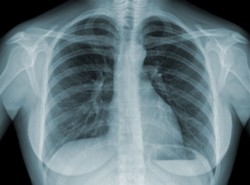

Do leczenie gruźlicy nie tylko antybiotyki, ale i witamin D/Shutterstock

Gruźlica od lat nieprzerwanie zabija. Mówi się, że w wielu przypadkach jest nieuleczalna. Pewną nadzieję dają wyniki najnowszych badań naukowców. Wykazali oni, że działanie antybiotyków jest skuteczniejsze, jeśli do leczenie włączy się witaminę D.

Przed antybiotykami do leczenia gruźlicy wykorzystywano słońce (tzw. helioterapia) - chorym zalecano opalanie się, by zmusić organizm do wytwarzania witaminy D. Ta terapia była wykorzystywana również w leczeniu innych schorzeń płuc. Teraz przypominają ją naukowcy z Queen Mary University of London. Jak dowodzą w "Proceedings of the National Academy of Science", witamina D pomaga zwyciężyć z gruźlicą.

Naukowcy zaobserwowali, że chorzy, którzy oprócz antybiotyków przyjmowali witaminę D, szybciej wracali do zdrowia i to o dwa tygodnie. A to niezwykle ważne, gdyż im krótsze jest leczenie, tym mniejsze uszkodzenia płuc.